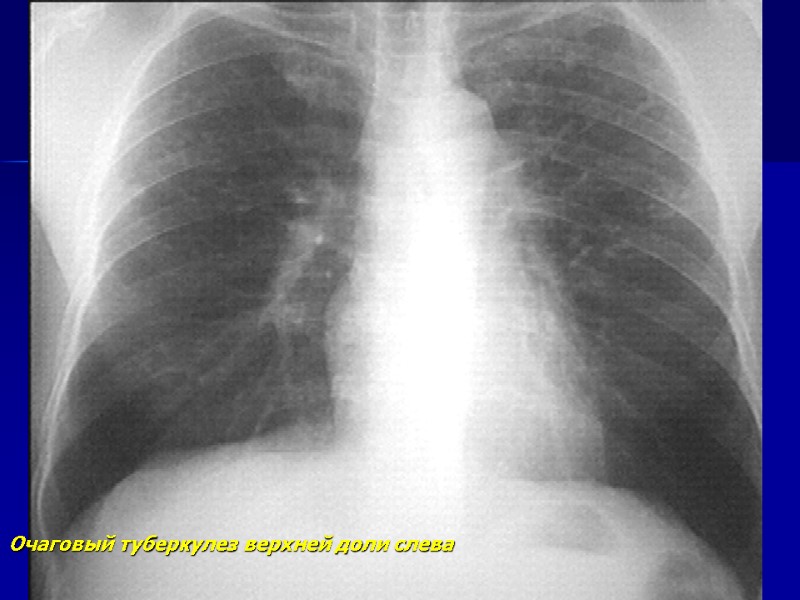

Очаговый туберкулез верхней доли слева